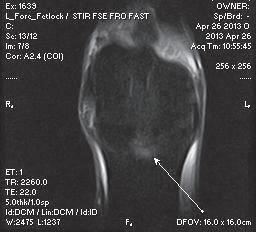

Figure 13: Nuclear scintigraphic image (left) showing focal zone of IRU on the proximal aspect of the left front first phalanx (P1) and corresponding dorsal plane MRI STIR image demonstrating subchondral osseous fluid associated with subchondral bone injury which was associated with an incomplete sagittal sulcus fracture.

Image courtesy of Dr. Richard D. Mitchell.

An example of a purchase examination where MRI was very helpful follows: The horse in question was a 12-year-old Grand Prix Dressage horse that had been successfully competing in FEI classes in Europe. Physical examination was unremarkable except for positive distal limb flexion tests in both forelimbs. There was no apparent lameness working on a lunge or under saddle. Radiographs indicated some varying bone densities in the subchondral bone of proximal P1in both forelimbs, suggestive of subchondral bone injury. An MRI unit was conveniently located nearby and an examination was recommended. A standing MRI examination of both fore fetlock regions was performed. Radiographic and MRI images are shown in Figure 16 and 17. Significant pathology was identified in the subchondral bone of proximal P1 in both forelimbs on radiography that appeared to be active on MRI (bone fluid or edema) (Figure 15). The horse was also discovered to have similar radiographic lesions in the RH fetlock.

The right fore fetlock appeared to have a more distinct area of intraosseous fluid signal and subchondral defects that presented a high risk for affecting future soundness (Figure 17). Th is information resulted in the buyer declining the purchase of the horse.